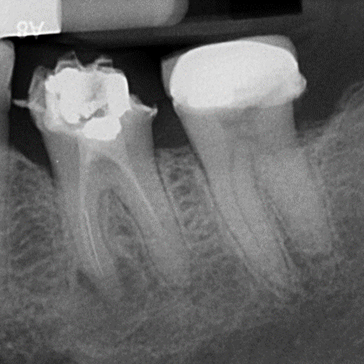

Root Canal Cases by Dr Mo Shibl

Case 1. Re-RCT of LL6

Case 2. RCT of UL6

Case 3. Re-RCT of UR6

Case 4. Re-RCT of LR6